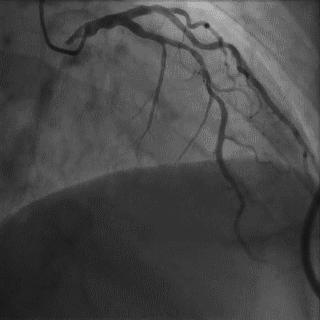

(2)冠脉开口异常

常规造影导管不易找到异常冠脉口部,或造影结果不清楚。

第一步:在主动脉窦部行非选择性造影(包括升主动脉造影),寻找异常开口位置;

第二步:更换特殊的造影导管,如AL1.0,AL1.5或其它。

➢ CASE 1

➢ CASE 2

右冠起源异常,开口于左冠窦